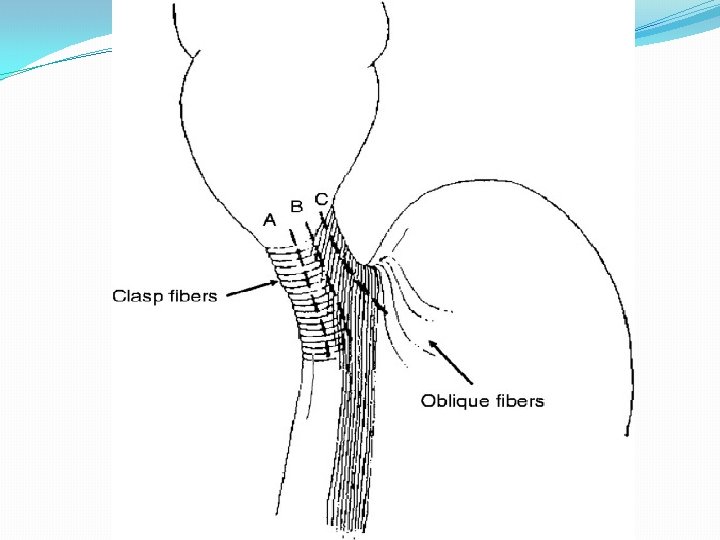

Surgical treatment �Esophageal myotomy for achalasia was first described by Ernest Heller in 1913. �In this operation, both the anterior and posterior lower esophageal sphincter muscle fibers were disrupted. �A modified version of this procedure, referred to today as the Heller myotomy, consists of a single anterior longitudinal myotomy and has become the standard operative technique. performed through either a thoracotomy or laparotomy.

Fundoplication ? �An anterior partial fundoplication (Dor ) �Anterior fundus is laid across the myotomy site and sewn to the cut edge of the esophageal myotomy with three or four interrupted sutures of 2 -0 silk. �Highest stitch is taken through the crural pillar as an anchor to prevent torsion of the fundus.

Fundoplication ? �Posterior partial fundoplication (Toupet), �The anterior fundus is brought to either side of the myotomy, and two columns of sutures are placed on either side, leaving the myotomy site bare and open

Extent of myotomy �Better symptomatic improvement and a lower incidence of recurrent dysphagia by increasing the distal extent of myotomy onto the proximal stomach from 1. 5 cm to 3 cm �Postoperative 24 -hour p. H data showed that extension of the distal aspect of the myotomy did not result in a higher prevalence of gastroesophageal reflux.